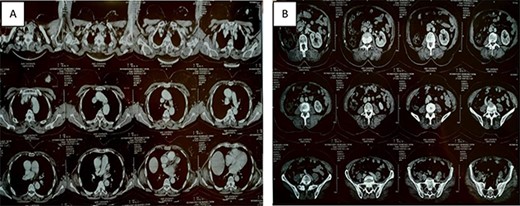

Six months ago, the patient was referred to our facility by a general practitioner for the management of a nodule of the left breast, with a left breast mass in the upper external quadrant, tissue, about 2.5 cm long axis, poorly limited and irregular (Fig. 1).

Thoracic-abdominal and pelvic computed tomography (CT) images showing on the thoracic level (A) a poorly limited mass measuring 27 × 22mm in the upper outer quadrant of the left breast (B) and a single left kidney at the abdomino-pelvic level.